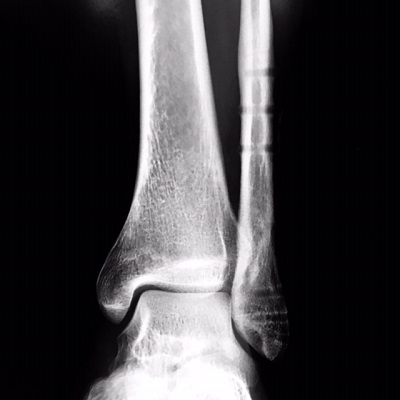

左遠位端骨折抜釘手術

今年1月に左足首を骨折した際に

2×4金物のようなものを足首に埋込み、

離れた骨を繋げる手術をしたのですが、

その2×4金物のようなものを取除く手術をしました。

それまで約10ヶ月間左足首に違和感がありましたが、

取除いたことでとてもスッキリしてます。